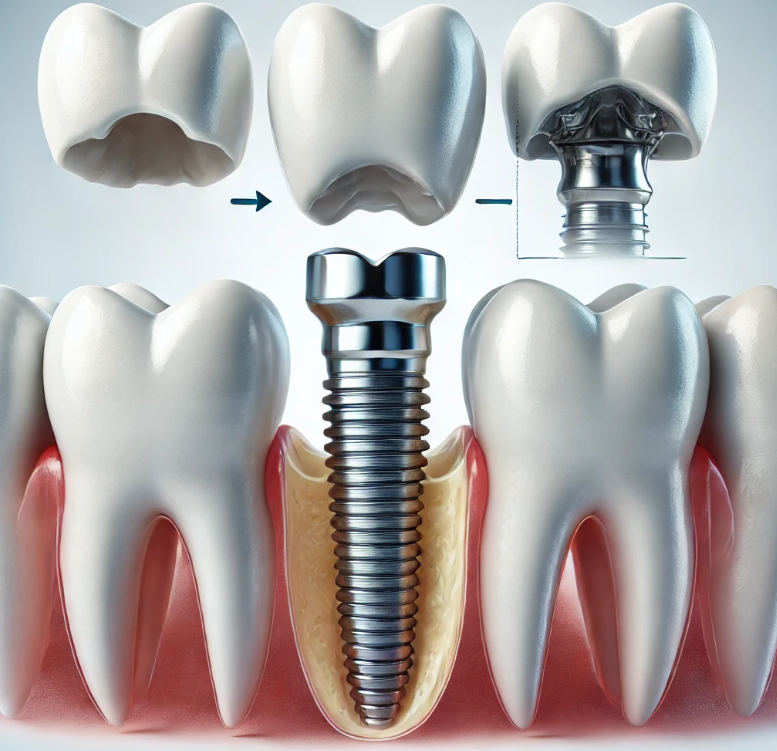

2. 임플란트 식립

임플란트 식립 단계에서는 티타늄으로 된 인공 치근을 잇몸 속에 심습니다. 티타늄은 인체에 잘 맞고, 시간이 지나면서 뼈와 융합되므로 안정적입니다. 이 과정은 국소마취로 이루어지며, 환자는 통증을 거의 느끼지 않습니다. 임플란트를 심고 나면 몇 달 동안 뼈와 임플란트가 잘 융합되도록 기다리는 기간이 필요합니다. 일반적으로 이 기간은 3개월에서 6개월 정도가 소요됩니다.

3. 임플란트 지대주 부착

뼈와 임플란트가 안정적으로 융합된 후, 지대주라는 작은 부품을 임플란트에 부착합니다. 이 지대주는 인공 치아와 임플란트를 연결하는 역할을 하며, 이후 인공 치아가 올바르게 장착될 수 있도록 도와줍니다.

4. 인공 치아 장착

마지막으로, 인공 치아를 제작하여 지대주 위에 장착합니다. 이 인공 치아는 환자의 치아 모양과 색상에 맞춰 맞춤 제작되며, 자연스러운 외관과 편안한 착용감을 제공합니다. 이렇게 완성된 어금니 임플란트는 자연치와 동일한 기능을 수행하게 됩니다.